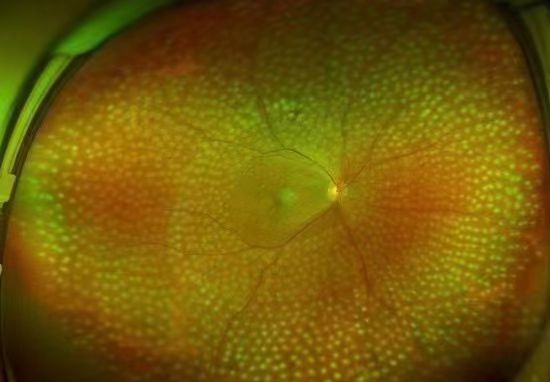

視網膜激光光凝:采用激光的熱凝效用,在局部出血部位和(或)無灌注區形成凝固激光斑,達到止血、預防再出血的效果。該治療為增殖期病變的首選治療方式,較早實行全視網膜光凝能有效預防失明,且價格低廉,效果較好。

激光光凝治療

視網膜激光光凝術是治療糖尿病性視網膜病變(DR)的重要手段,分為全視網膜激光光凝(PRP)、黃斑格柵樣激光光凝等。激光光凝術是高危增殖性糖尿病性視網膜病變(DR)患者及某些嚴重非增殖性患者的主要治療方式。

激光治療旨在減少視力進一步下降的危險,盡量保護視功能。高危增殖性糖尿病性視網膜病變患者應迅速施行全視網膜激光光凝治療。約50%的重度非增殖性糖尿病性視網膜病變患者在1年內可進展為增殖性糖尿病性視網膜病,15%進展為高危增殖性糖尿病性視網膜病,若病情進展應考慮行全視網膜激光光凝治療。

在激光之前,若已經出現明顯的黃斑水腫,應先治療黃斑水腫,因大面積的視網膜光凝,會導致黃斑水腫的進一步加重。以前,臨床通常采用口服藥物或者先對黃斑進行光凝的處理,近年來,更多采用抑制血管內皮生長因子的方法處理黃斑水腫問題。

全視網膜激光光凝術后

在結束激光治療時,很多患者會表示視力反而不如治療前。這種現象,實際是激光過程中,對視網膜產生了彌漫性的光漂白作用,通常半小時左右的時間就可以恢復,不需要特殊處理。總體來說,激光治療是安全且并不會導致失明的。